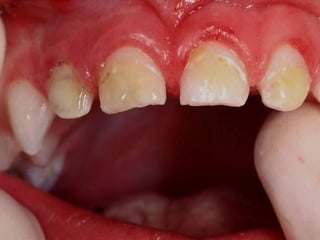

Es más frecuente

en niños que se

quedan dormidos

con el biberón

Esto tiene un papel

biológico al provocar

la desmineralización

de los dientes

Las primeras lesiones no son cavitadas

a medida que pasan los años

aparecen más lesiones cavitadas